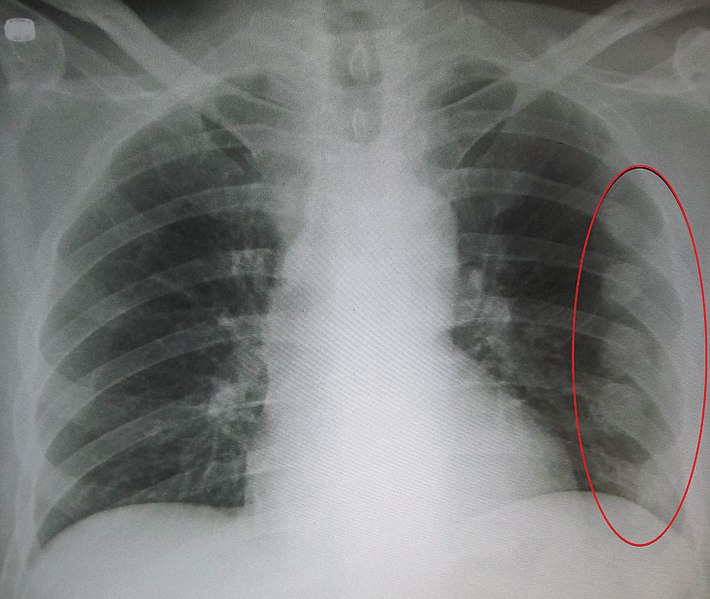

صورة الصدر البسيطة CXR، قد نشاهد فيها:

• كسور في الأضلاع

قد لا تظهر الصورة الشعاعية أي كسر حتى 2-3 أسابيع بعد الرض، لذا فإن سلبية الصورة البسيطة لا ينفي وجود الكسر، لذا فاعتمادنا الأساسي في تشخيص الكسر على الموجودات السريرية حتى يثبت العكس.

رضوض الأضلاع : صورة أشعة بسيطة تظهر وجود كسر في الأضلاع على الجهة اليسرى من القفص الصدري

استرواح أو تدمي الجنب أو كليهما (سوية سائلة هوائية).